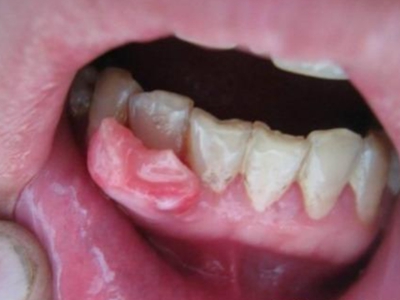

牙龈癌多源于牙间乳头及龈缘区,溃疡呈表浅、淡红,以后可出现增生。由于黏骨膜与牙槽突附着甚紧,较易早期侵犯牙槽突骨膜及骨质,进而出现牙松动,并可发生脱落。X线片可出现恶性肿瘤的破坏特征虫蚀状不规则吸收。

牙龈癌常发生继发感染,肿瘤伴以坏死组织,触之易出血。体积过大时可出现面部肿胀,浸润皮肤。